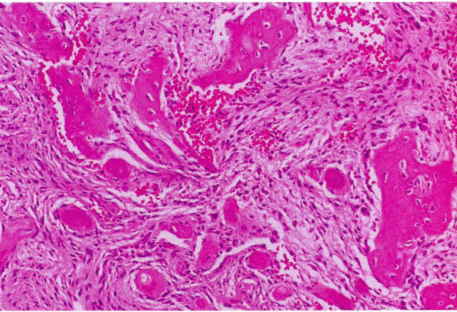

Патологическая анатомия цементно-костной дисплазии. Все три формы цементно-костной дисплазии выглядят одинаково при гистологическом исследовании и состоят из фрагментов мезенхимальной ткани, фибробластов и коллагеновых волокон с многочисленными небольшими кровеносными сосудами; типичны кровоизлияния, проходящие через всё поражение. Между соединительной тканью располагаются костные трабекулы и цементоподобные частицы (рис. 2).

Рис. 2. Гистология цементно-костной дисплазии, начальное увеличение х400

Пропорции каждого минерализованного материала варьируют от поражения к поражению, от зоны к зоне, по мере созревания делаются более склеротическими, соотношение соединительной ткани к минерализованному материалу уменьшается. В финальной радиоплотной стадии костные трабекулы сливаются в дольчатые массы, состоящие из полос или слившихся относительно бесклеточных глобул и дезорганизованного цементно-костного материала.